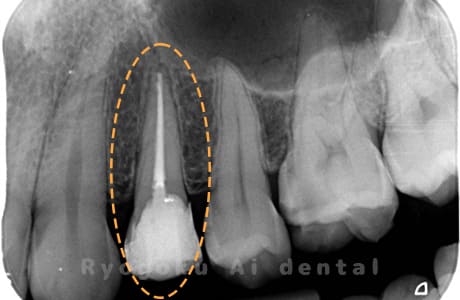

Case01

根管内の異物

- 原因

- 根管内異物(ファイル破折)による慢性根尖性歯周炎

- 治療期間

- 3ヶ月

- 治療内容

- マイクロスコープを使用した根管内異物除去並びにマイクロエンド

- 治療費用

- 121,000円(ファイル除去費用も込み)

他院で細い器具(ファイル)が根管内に破折した状態で、咬合痛を主訴に来院された患者様です。ファイルをマイクロスコープ下で除去し、根管治療を行ないました。

<リスク・副作用>

術後は痛み、腫れ、痺れなどの副作用が生じる場合があります。症状が再発する可能性があります。